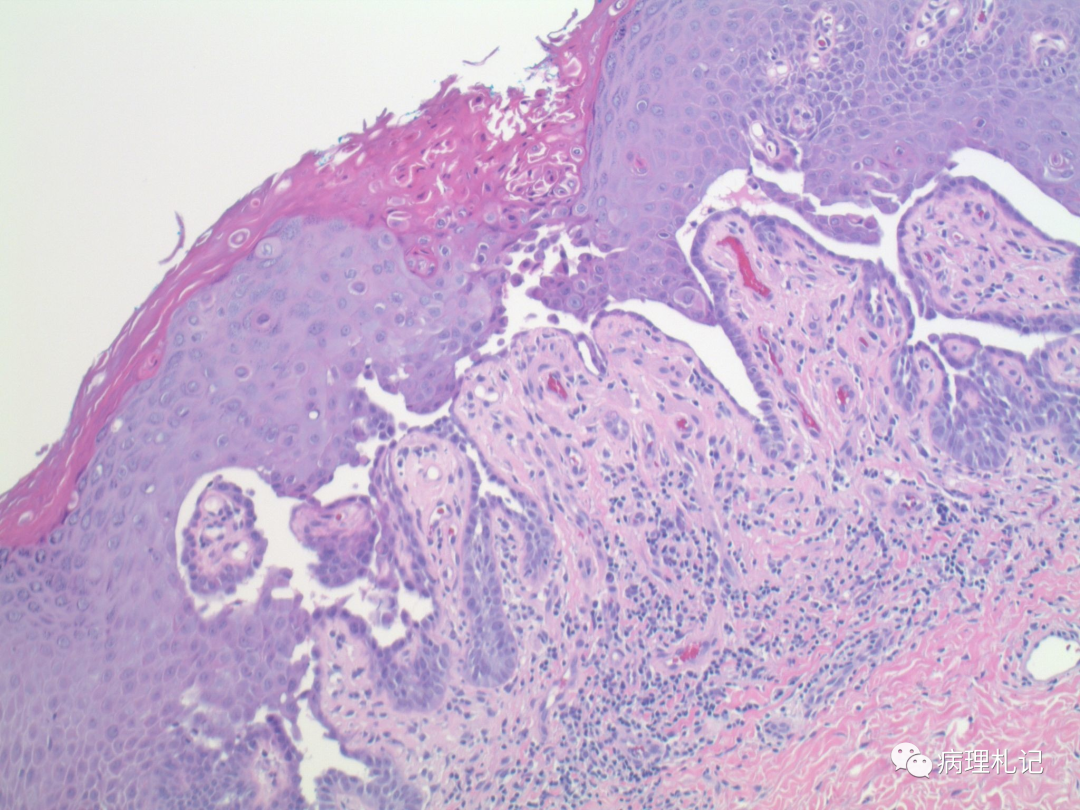

弥漫性神经纤维瘤中惊叹wagnermeissner小体